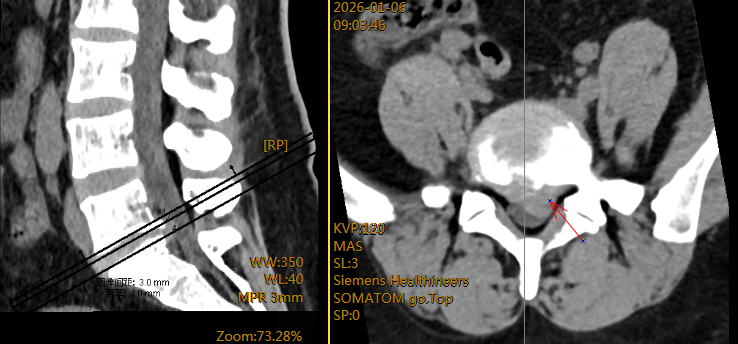

入院后,专科检查显示左下肢直腿抬高试验及加强试验在30度即呈阳性,是神经根受到牵拉刺激的明确体征。结合腰椎核磁共振(MRI)这一“金标准”影像学检查,清晰显示腰5-骶1节段左侧椎间盘突出,并压迫到左侧神经根,诊断明确。对于经系统保守治疗,如休息、药物治疗、康复理疗等无效,或症状严重、出现神经功能损害迹象的患者,手术干预是解除压迫、根治症状的有效手段。

术前腰椎MRI平扫示间盘CT示腰5-骶1椎间盘左侧突出,压迫左侧神经根